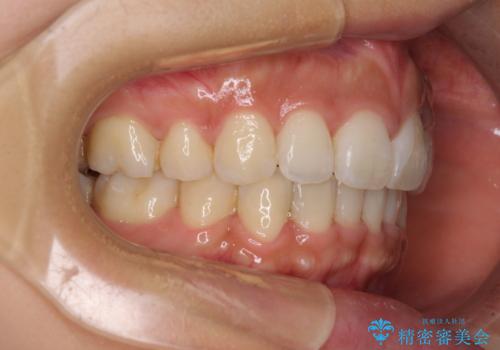

- 上下の出っ歯を気にして来院された患者様です。

口元を積極的に引っ込めるために、上下左右の第一小臼歯を4本抜歯することとしました。

下顎の正中を上顎に合わせる処置が難航し、期間が長引きました。

最終的には上下の正中も合い、横顔の印象が変わるほどスッキリとした口元となりました。